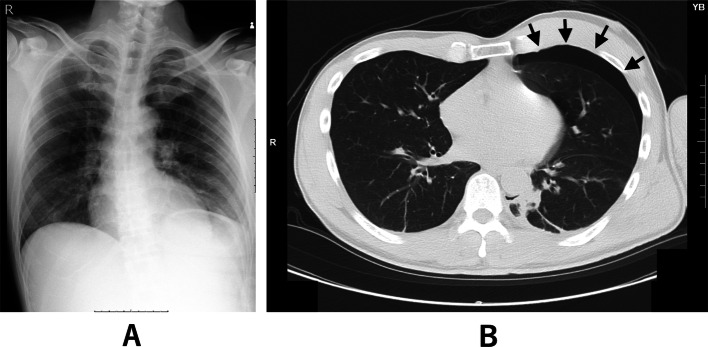

Case presentation: A man in his 50 s with a left clavicle fracture and mild left-sided occult pneumothorax on computed tomography was scheduled for surgery under general anesthesia. Conservative management was chosen given the absence of respiratory symptoms and stable imaging. To minimize the risk of pneumothorax progression during positive pressure ventilation, one-lung ventilation was employed to avoid ventilating the affected lung. Surgery proceeded uneventfully, with transient hypoxemia that was managed by increasing FiO2 to 100%. Postoperative imaging confirmed re-expansion of the left lung and no pneumothorax progression. The patient was discharged in good condition.